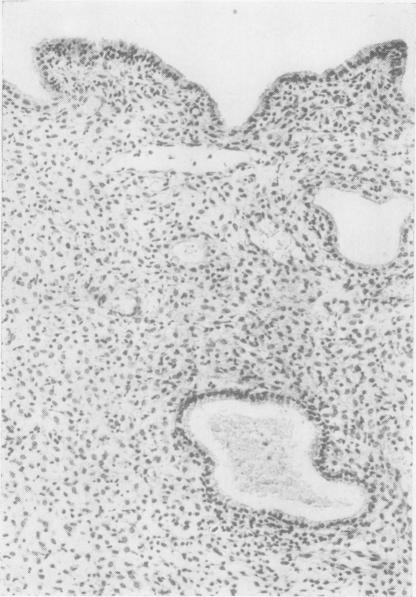

19-nor steroids in high and medium dosage in continuous or cyclic combined regimens with oestrogen produce an endometrium characterized by hyperinvoluted glands, a prominent predecidual reaction, suppressed arterioles, and dilated venules. When daily dosage is decreased to 2.0 mg. or less, the endometrium is composed of hyperinvoluted glands in an inert stroma; predecidual reactions are weak and infrequent; venules are rarely dilated, but spiral arterioles are suppressed.17-alpha-Acetoxyprogesterone derivatives in high and medium dosage given in a cyclic combined regimen with oestrogen produce similar but less intense effects to the 19-nor steroids. When given in cyclic sequential regimen, they produce an early secretory endometrium closely resembling normal patterns, chronologically retarded by about five days; in some instances a regressing, undatable secretory pattern is found, but predecidual response is minimal, and dilated venules are not seen.19-nor steroids in medium dosage given for 20 days without added oestrogen produce a late secretory endometrium with unpredictable variation from patient to patient and even from site to site within the same endometrium. Inhibition of the development of spiral arterioles is a common denominator in all progestagenoestrogen regimens. Modification of this element within the target tissue may be decisive for the morphogenesis of later vascular and stromal changes. Using synthetic progestagen-oestrogen regimens, endometrial gland secretion appears only after progestagen, whether given ab initio concomitantly with oestrogen or begun after a phase of oestrogen priming. Secretory vacuoles become evident about four to five days after progestagen is administered. The role of progestagen in secretion is interpreted as an indirect effect whereas its role in the development of decidual-like changes is construed as direct.

19-去甲甾体类药物以高剂量和中等剂量与雌激素连续或周期性联合使用时,会使子宫内膜呈现出以下特征:腺体过度退化、明显的蜕膜前反应、小动脉受抑制以及小静脉扩张。当每日剂量降至2.0毫克或更低时,子宫内膜由处于惰性基质中的过度退化腺体组成;蜕膜前反应微弱且不常见;小静脉很少扩张,但螺旋小动脉受到抑制。17-α-乙酰氧基孕酮衍生物以高剂量和中等剂量与雌激素周期性联合使用时,会产生与19-去甲甾体类药物相似但程度较轻的效果。当以周期性序贯方案给药时,它们会产生一种早期分泌期子宫内膜,与正常模式非常相似,但时间上延迟约五天;在某些情况下,会发现一种退行性、无法确定日期的分泌模式,但蜕膜前反应极小,且未见小静脉扩张。19-去甲甾体类药物以中等剂量连续20天给药且不添加雌激素时,会产生晚期分泌期子宫内膜,不同患者之间甚至同一子宫内膜内不同部位之间都存在不可预测的差异。抑制螺旋小动脉的发育是所有孕激素-雌激素方案的共同特征。在靶组织内对这一要素的改变可能对后期血管和基质变化的形态发生起决定性作用。使用合成孕激素-雌激素方案时,无论孕激素是一开始就与雌激素同时给药,还是在雌激素预处理阶段之后开始给药,子宫内膜腺体分泌都只会在给予孕激素之后出现。在给予孕激素约四到五天后,分泌空泡变得明显。孕激素在分泌中的作用被解释为间接作用,而其在蜕膜样变化发展中的作用则被认为是直接作用。